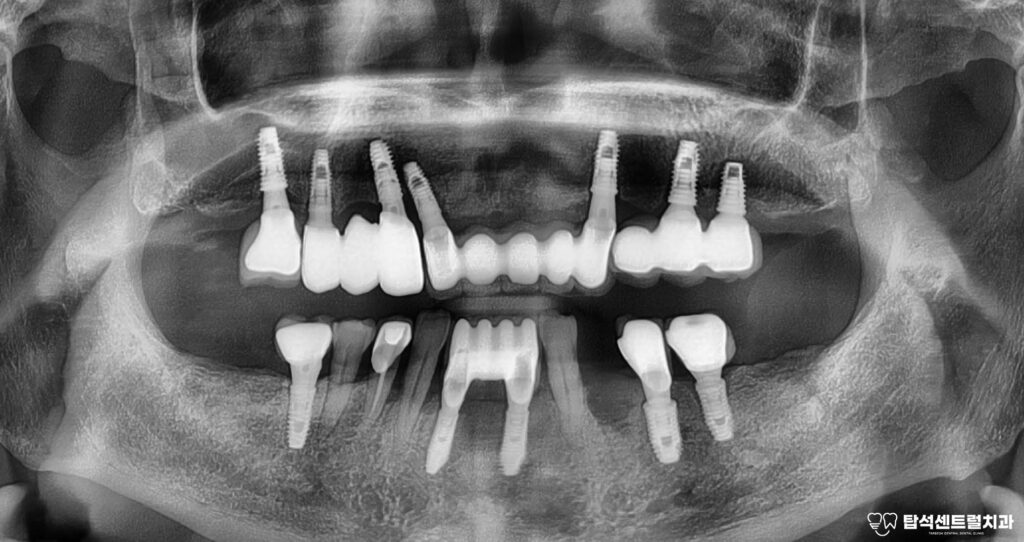

치아 주변으로 골소실이 진행되면

방사선 사진에서 뼈가 빠져나간 부분이

검게 보이게 됩니다.

뼈가 녹아내리는 속도는 개인마다 다르지만

한번 시작되면 점점 빨라지는 경향이 있어

조기 발견이 중요합니다.

골소실이 심하게 진행된 고정체는

보존이 어려워 제거해야 될 수 있습니다.

흔들리는 상태에서 무리하게 사용하면

주변의 건강한 뼈까지 손상될 수 있기 때문입니다.

제거한 픽스처의 모습입니다.

염증이 퍼지면서 인접한 자연치아나

다른 고정체에도 영향을 줄 수 있어,

적절한 시기에 결단을 내리는 것이 중요합니다.

다행히, 왼쪽 위턱의 송곳니는 상태가 양호하여

임플란트 한개 제거 후 장기적인 안정성을

위해 앞니에 2개의 임플란트 를

추가 식립한 모습입니다.